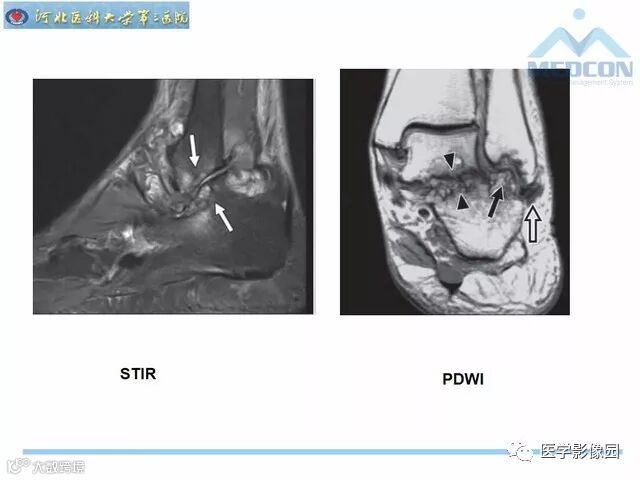

踝关节撞击综合征影像诊断,干货满满,值得收藏!

导读:踝关节撞击综合征影像诊断。干货满满,值得收藏!

踝关节撞击综合征影像诊断。干货满满,值得收藏!